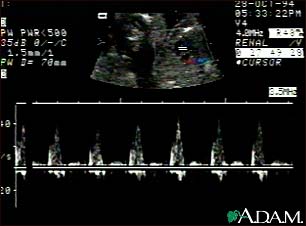

Ultrasound, normal fetus - heartbeat

This is an ultrasound showing a ventricular septal defect pattern of the fetal heartbeat. Some ultrasound machines have the ability to focus on different areas of the heart and evaluate the heartbeat. This is useful in the early diagnosis of congenital heart abnormalities.